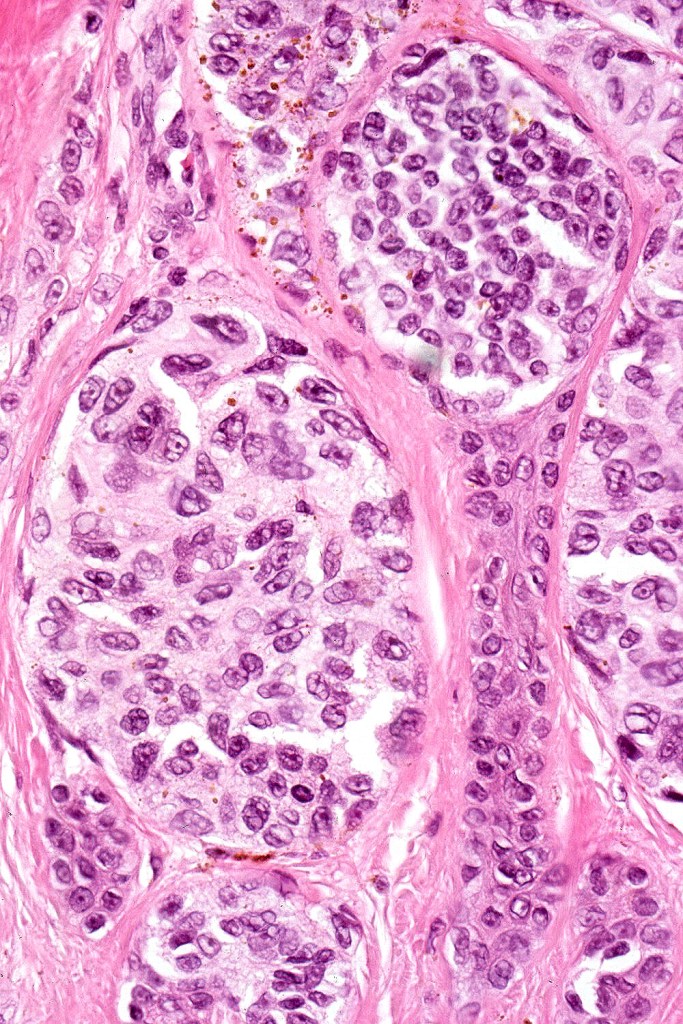

•Diffuse infiltrate of nevus cells often extending deeply into the dermis or beyond, single filing is often present at base & may involve the septa of the subcutaneous fat

•Neurotization, neurofibroma-like lesions & neurocristic hamartoma

•Perineural sheath infiltration

•Blood vessel and lymphatic wall infiltration

•Superficial mitotic activity